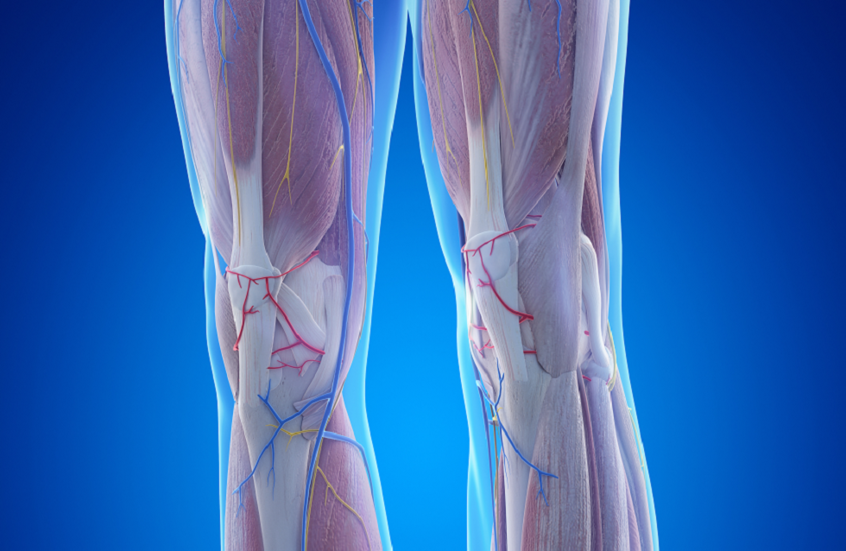

عامل خفي في العضلات قد يزيد خطر فقدان الأطراف

تكشف دراسة علمية جديدة أن ضعف العضلات لدى مرضى الشرايين المحيطية قد لا يرتبط فقط بضعف تدفق الدم، بل أيضا بتراكم الدهون داخل العضلات نفسها.

وقد يفسّر هذا العامل استمرار ضعف القدرة على المشي لدى كثير من المرضى حتى بعد العلاج.

ويعدّ مرض الشرايين المحيطية اضطرابا وعائيا يصيب أكثر من 200 مليون شخص حول العالم، ويتسبب في تضيق شرايين الساق غالبا نتيجة تراكم اللويحات داخل الأوعية الدموية. ومع انخفاض تدفق الدم، يعاني المرضى عادة من ألم في الساق، خصوصا أثناء المشي.

وفي المراحل المتقدمة من المرض قد يتطور الوضع إلى ما يعرف بنقص التروية المزمن المهدّد للأطراف، وهو انخفاض حاد في تدفق الدم قد يؤدي في النهاية إلى بتر الطرف المصاب.

ولسنوات طويلة ركّزت العلاجات المتاحة على إعادة فتح الشرايين وتحسين تدفق الدم، سواء عبر الجراحة أو من خلال تحفيز نمو أوعية دموية جديدة. إلا أن كثيرا من المرضى يظلون يعانون ضعفا عضليا شديدا حتى بعد نجاح هذه الإجراءات.

وفي دراسة حديثة، وجد باحثون من جامعة فلوريدا أن تراكم الدهون داخل العضلات الهيكلية — على غرار التبقّع الدهني في شريحة اللحم — يؤثر مباشرة في قدرة العضلات على العمل لدى المرضى المصابين بمراحل متقدمة من المرض.

ويشير الباحثون إلى أن هذه الدهون داخل العضلات ليست مجرد نتيجة لمرض الأوعية الدموية، بل قد تكون أحد الأسباب المباشرة لضعف الأطراف.

وقال الدكتور تيرينس رايان، الأستاذ المشارك في قسم علم وظائف الأعضاء التطبيقي وعلم الحركة في جامعة فلوريدا، إن الخيارات العلاجية المتاحة حاليا لمساعدة المرضى على تحسين قدرتهم على المشي ما تزال محدودة.

وأضاف أن العلاجات الحالية تركز أساسا على تحسين تدفق الدم، لكنها لا تعالج مشكلة تراكم الدهون داخل العضلات، ما يستدعي دراسة العوامل التي تؤثر في وظيفة الساق بصورة أدق وتطوير أساليب علاجية جديدة.

وعند تحليل عينات من عضلات الساق لدى مرضى يعانون تضيقا متقدما في الشرايين، لاحظ الباحثون أن الجينات المسؤولة عن تكوين الخلايا الدهنية كانت أكثر نشاطا بكثير مقارنة بالأشخاص غير المصابين بالمرض.

وأوضح الدكتور دانيال كوبينك، الأستاذ المشارك في قسم علم الأدوية والعلاجات بكلية الطب في جامعة فلوريدا، أن زيادة الدهون داخل أنسجة العضلات ترتبط بتراجع أداء العضلات.

وللتأكد مما إذا كانت الدهون سببا في هذا الضعف أم نتيجة له، أجرى الباحثون تجارب على الفئران، فقيّموا وظائف العضلات ونسبة الدهون داخلها. وأظهرت النتائج أن العضلات تصبح أضعف بوضوح عندما تتراكم فيها الدهون، حتى في حال استعادة تدفق الدم الطبيعي.

كما لاحظ الباحثون أن تعديل العملية التي تنظم بها بعض البروتينات إنتاج الدهون أدى إلى تحسن أداء العضلات، حتى دون تغيير تدفق الدم إلى الأطراف.

وتشير هذه النتائج إلى أن بنية العضلات نفسها قد تلعب دورا مهما في تطور المرض، وهو ما يفتح المجال أمام نهج علاجي مختلف لا يقتصر على الشرايين فقط، بل يستهدف أيضا منع تراكم الدهون داخل العضلات.

ويأمل الباحثون أن تساهم الدراسات المستقبلية في تحديد العوامل التي تدفع إلى تراكم الدهون في عضلات الساق لدى المرضى الذين يعانون ضعف تدفق الدم، بما يساعد على تطوير علاجات تحسن قوة العضلات والقدرة على المشي، وتنعكس إيجابا على جودة حياة المرضى.

نشرت الدراسة في مجلة Circulation.